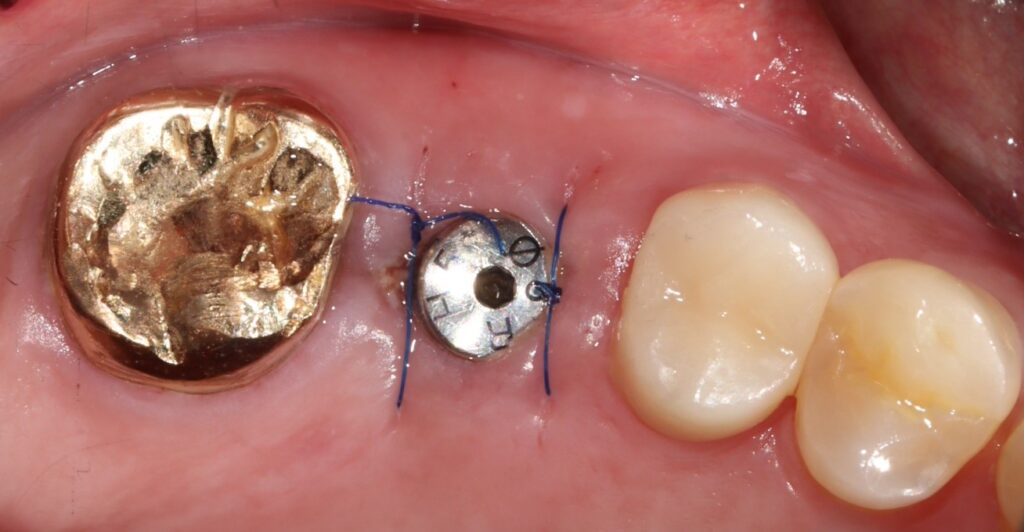

상악동의 치조정 방향에서 거상시켜

적절한 임플란트의 길이와 뼈를 만들어 주어

수술에서는 절개하지 않고 무절개 수술법을

이용했기 때문에 수술이 빠르고

통증 없이 마무리 하였습니다.

초기 고정력은 15N정도로 강한편은

아니었기 때문에 다시 3개월정도

기다렸다가 보철 시행까지 마무리를 하였습니다.